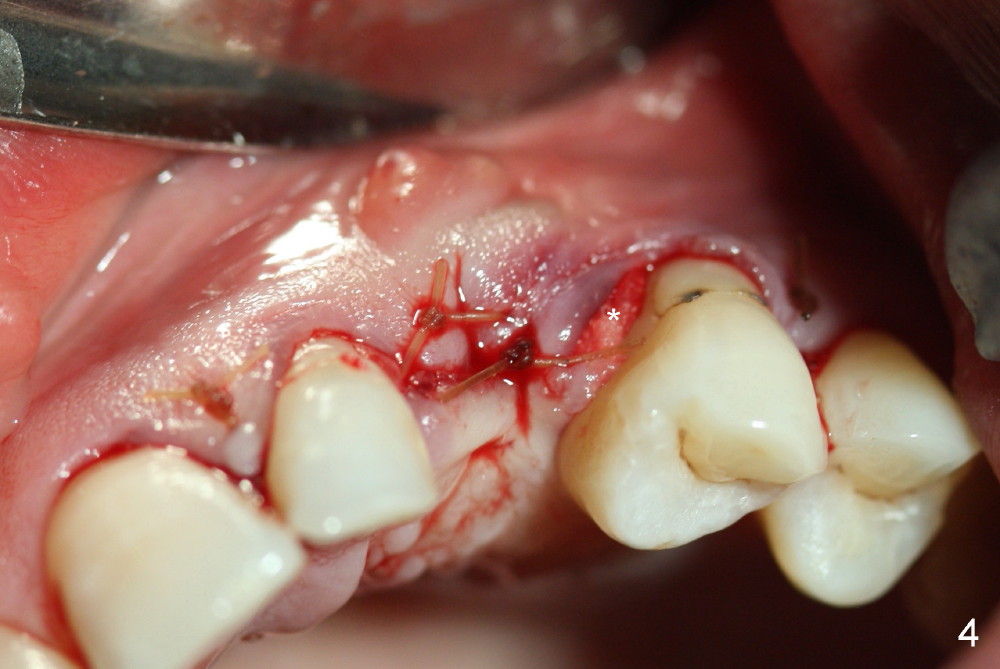

One month post-implantation at the site of the upper left deciduous canine, the patient returns for follow-up with chief complaint "The crown is a little loose. A bubble is becoming smaller". Exam shows an abscess (Fig.1 <) above the provisional (#11). The provisional is loose with mild tenderness. A pull on the provisional leads to dislodgement of the abutment and implant. Raising the buccal flap reveals perforation of the buccal plate with granulation tissue (Fig.2). After debridement (Fig.3), allograft and Osteogen is placed in the defect, followed by Osteotape (Fig.4 *) and suture. This complication can be prevented by CT information. A deciduous tooth socket is small. The immediate implant should be not too large, leaving 2 mm buccal gap. Three months 20 days post graft, the ridge looks not so atrophic (Fig.5). There is no sign of bone resorption (Fig.6). The patient will return for implant placement for the second time soon. Measure the bone width with bone caliper after local anesthesia. Fully expose the alveolus. Start osteotomy as palatal as possible. Repeatedly check osteotomy position and trajectory. Use surgical stent. The implant will not be too long or too wide. Is the ridge as wide as clinically shown?